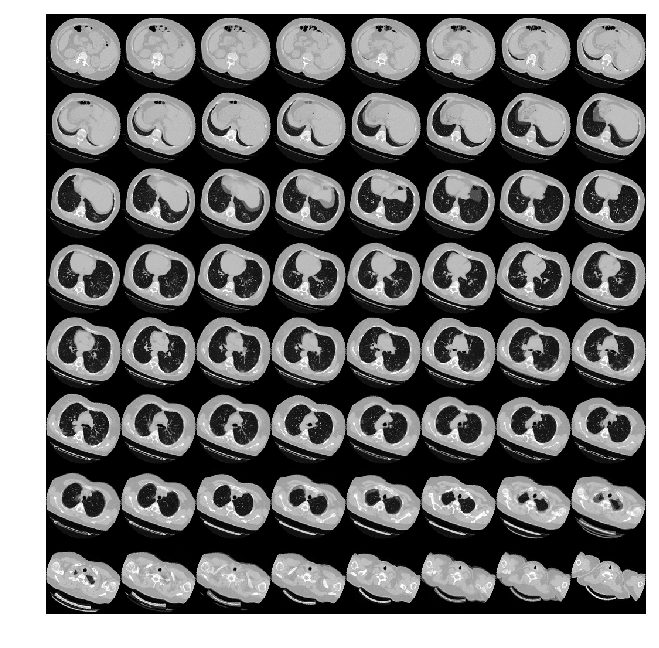

由于CT扫描有许多层切片,可视化多层切片。

def plot_slices(num_rows, num_columns, width, height, data):

"""绘制CT的横断面"""

data = np.rot90(np.array(data))

data = np.transpose(data)

data = np.reshape(data, (num_rows, num_columns, width, height))

rows_data, columns_data = data.shape[0], data.shape[1]

heights = [slc[0].shape[0] for slc in data]

widths = [slc.shape[1] for slc in data[0]]

fig_width = 6.0

fig_height = fig_width * sum(heights) / sum(widths)

f, axarr = plt.subplots(

rows_data,

columns_data,

figsize=(fig_width, fig_height),

gridspec_kw={"height_ratios": heights},

)

for i in range(rows_data):

for j in range(columns_data):

axarr[i, j].imshow(data[i][j], cmap="gray")

axarr[i, j].axis("off")

plt.subplots_adjust(wspace=0, hspace=0, left=0, right=1, bottom=0, top=1)

plt.show()

# 绘制CT横断面.

plot_slices(8, 8, 128, 128, image[:, :, :64])